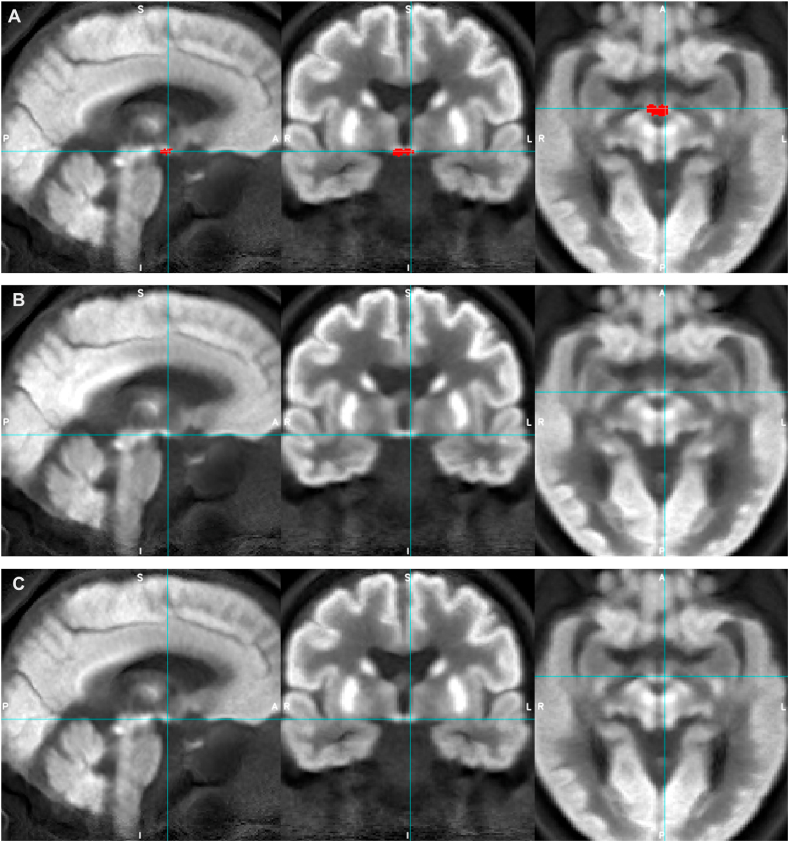

Fig. 5.

Appearances of the average group FDG-PET image for AD (rows A and C) and HC (row B) groups with mammillary bodies mask overlaid (red, row A, and blue crosshairs) to demonstrate mammillary bodies ROI location and its relative visibility compared to the LC.

Although the non-dilated LC ROIs (apart from Dahl LC ROI) were comparable to the bilateral mammillary body ROI both in terms of volume (between 78 and 195 mm3 and 130 mm3 respectively) and SUVR range (0.69–0.85 and 0.64–0.79 respectively), only the mammillary bodies showed significant group differences in median and maximum SUVR, with medium effect sizes (d = 0.5–0.6) and could be visualized on the average group PET images more clearly (Fig. 4, Fig. 5).